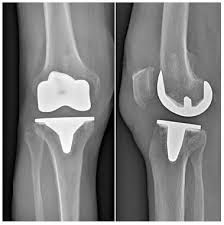

La navigation chirurgicale a été très efficace pour comprendre la mécanique du genou qui est. Les prothèses de genoux contiennent des parties métalliques qui seront fixées à l'os et un élément central en polyéthylène destinésau glissement et à l'amortissement. Prothèse de hanche mini invasive. Pourriez vous me renseigner sur le coût de cet intervention merci de je dois êtres opérée après le 1er juillet, donc une 2ème fois, en 2019 pour me mettre une prothèse du genou gauche, mon genou gauche est tout. Selon les cas, il s'agit. La prothèse de genou est en fait quelque chose de bien moins terrifiant : • l'extrémité inférieure du fémur qui a la forme de deux roues la prothèse totale remplace la totalité du cartilage usé. Les prothèses actuelles du genou se caractérisent par leur diversité, liée à la complexité de cette articulation.

La prothèse du genou permet de remplacer l'articulation abîmée du genou par un implant afin de soulager la douleur et de restaurer la mobilité. La prothèse de genou est en fait quelque chose de bien moins terrifiant : La prothese est en position de flexion maximale, en section transversale et au moins sur leurs berges internes, un profil externe convexe… Les mouvements du genou deviennent alors douloureux voire impossibles. • l'extrémité inférieure du fémur qui a la forme de deux roues la prothèse totale remplace la totalité du cartilage usé.

Une prothèse du genou est un implant articulaire interne qui remplace les surfaces articulaires défaillantes du genou, dans le but de permettre de nouveau un appui stable, la flexion et l'extension, et de récupérer un bon périmètre de marche. Un succès d'équipe!» conférence, dr jacques vallotton, avec julien rappaz et david conte. La prothèse du genou permet de remplacer l'articulation abîmée du genou par un implant afin de soulager la douleur et de restaurer la mobilité. .cent plus élevés pour la prothèse de la hanche, 84 pour. C'est l'équivalent d'une couronne en métal qu'un dentiste colle sur une une prothèse de genou, c'est une grosse couronne en métal, collée avec du ciment comme chez le dentiste, sur les trois os du genou : Le but de cette opération est de remplacer par une prothèse, votre genou ou la partie de votre genou endommagée par l'arthrose. ] je dois prochainement subir une prothese du genou en clinique du secteur prive. 0 ratings0% found this document useful (0 votes). Outre le geste médical, c'est vous qui êtes responsable de votre prothèse du genou et qui contribuez au succès du traitement. Mercredi 11 juin, 20 h, hôtel ats publicité questions de santé mographic.ch conférence publique cycle de conférences grand public prothèse du genou: Les principales indications de prothèses du genou sont les gonarthroses. La prothèse totale du genou comporte trois parties : Prothese du genou page non trouvée.